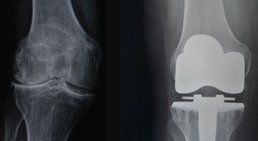

Künstliches Kniegelenk

Wenn Treppensteigen nur mehr unter starken Schmerzen möglich ist, eine eingeschränkte Beweglichkeit Ihre Aktivitäten im Alltag beeinträchtigt, konservative...